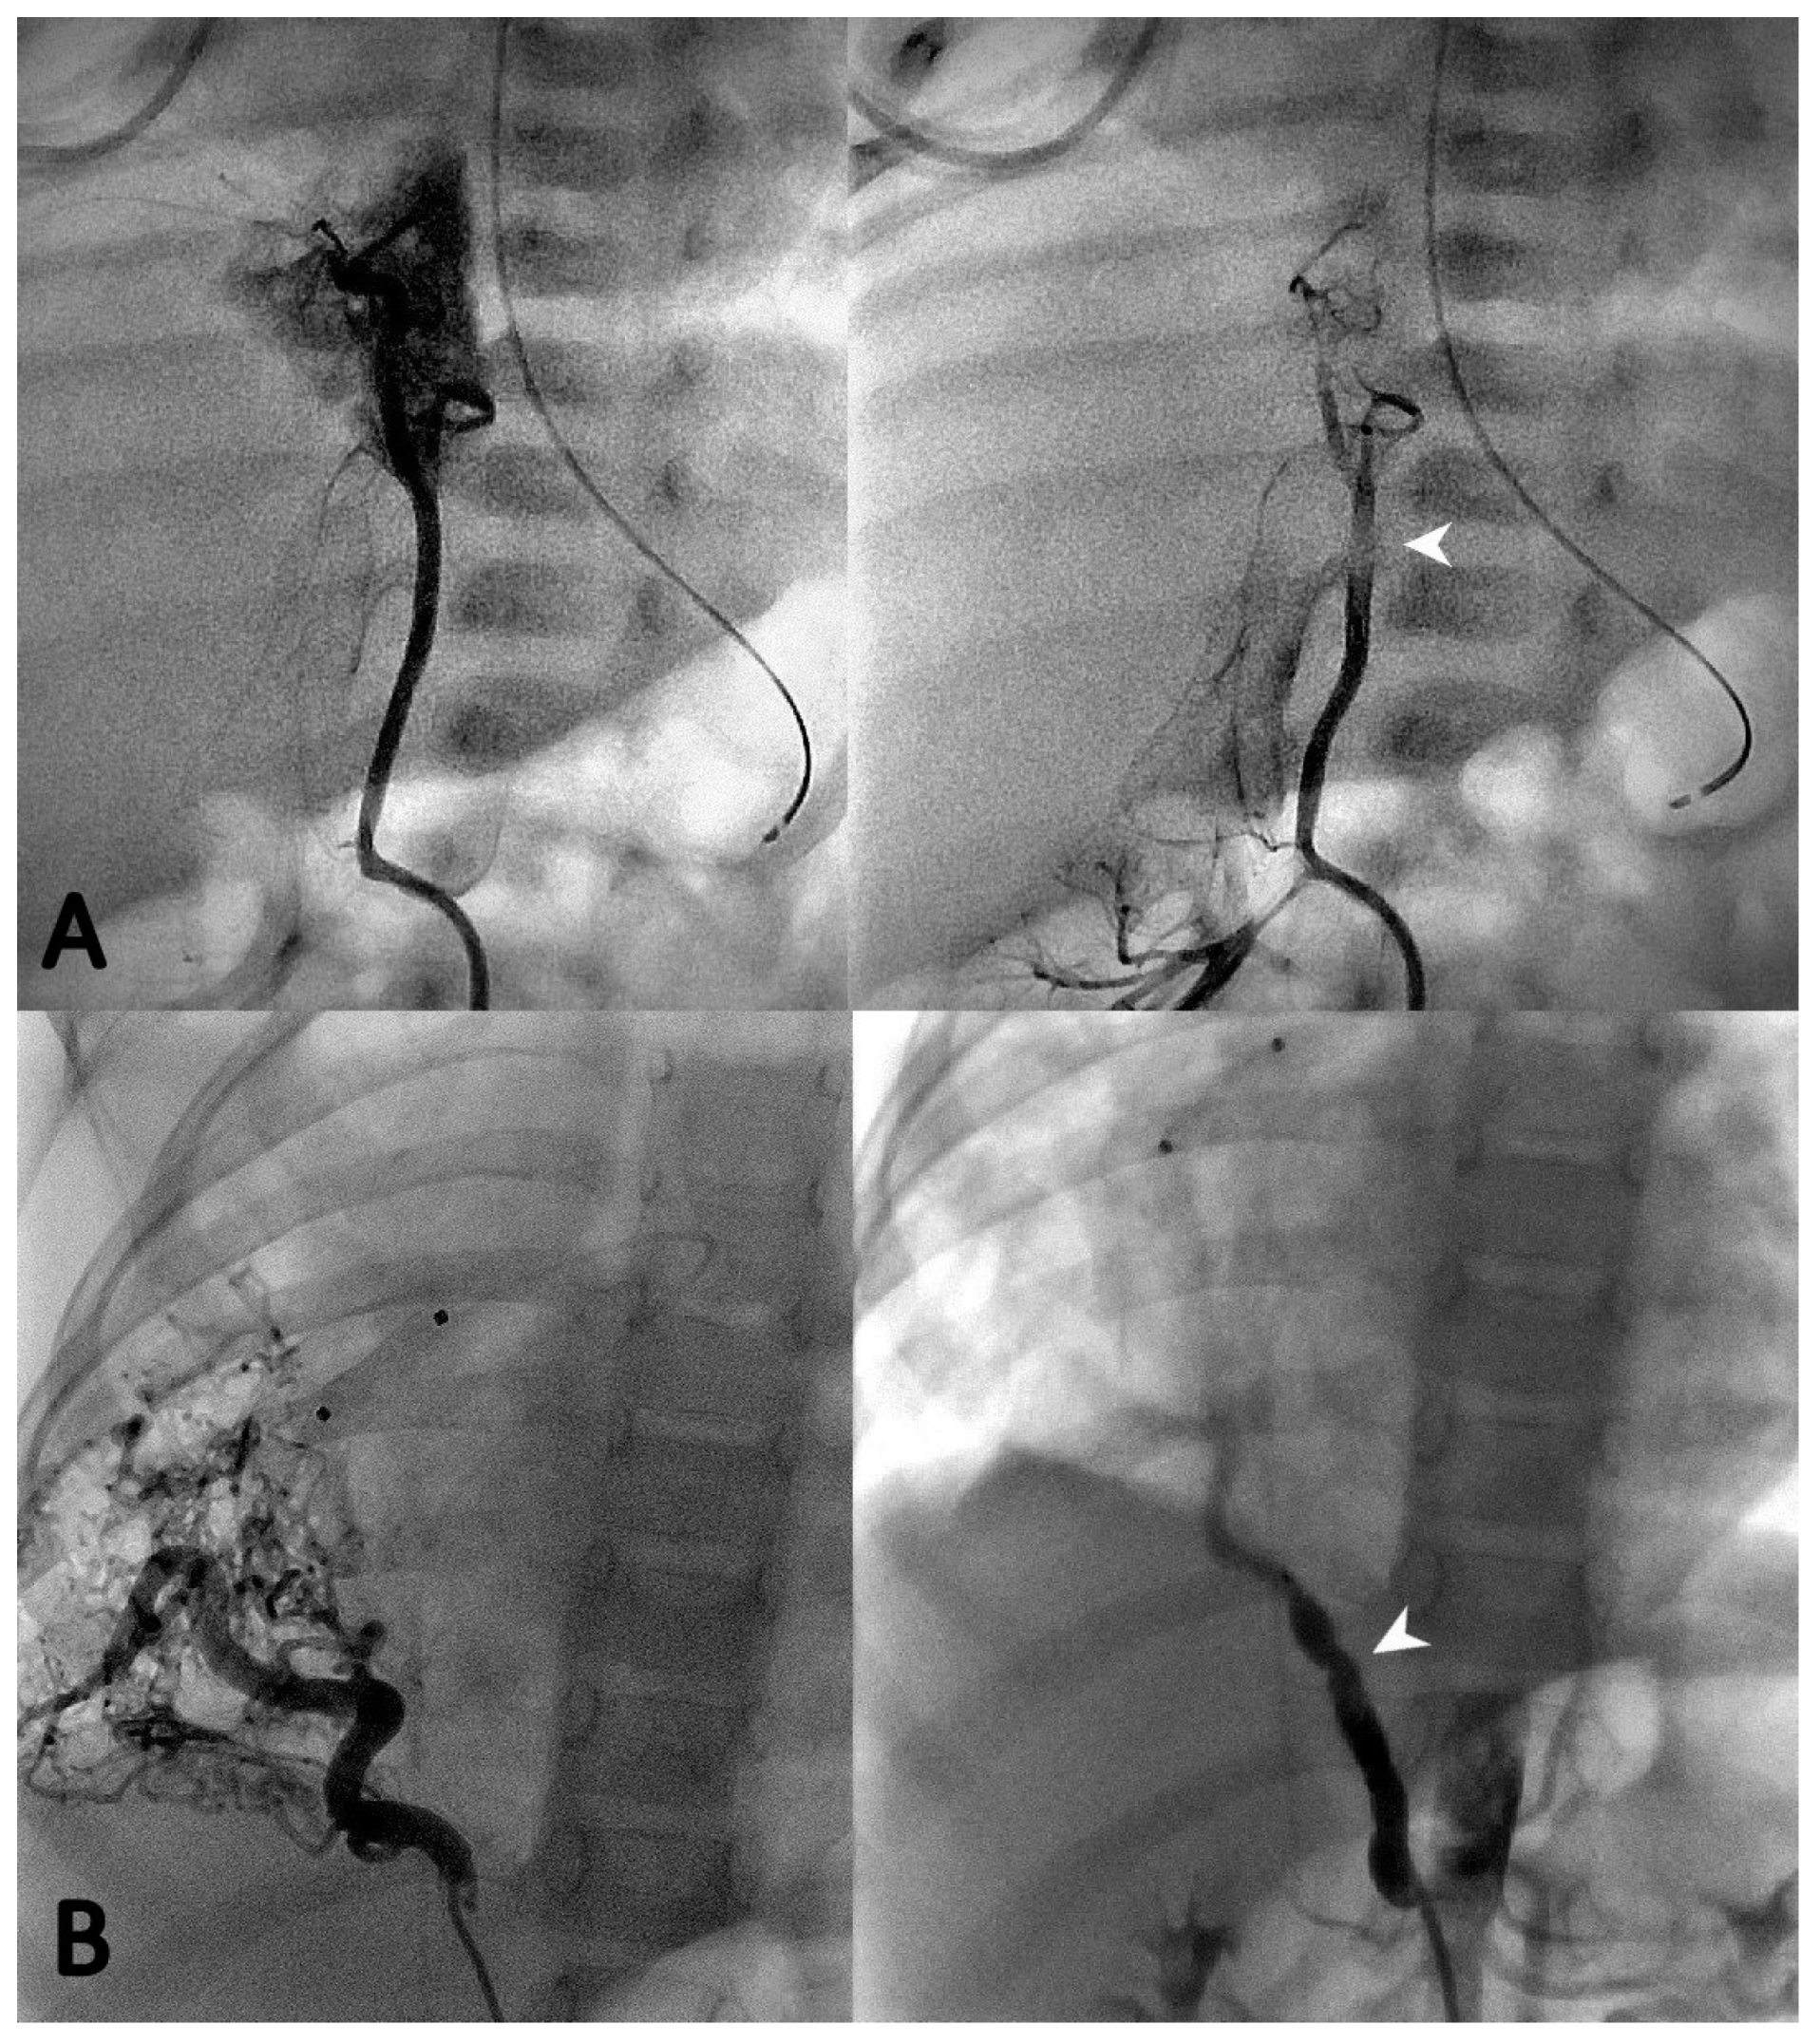

3.3. Endovascular Embolization

During the first procedure, 47/71 (66.2%) patients underwent endovascular embolization of the PS feeding vessel (Figure 1, Figure 2 and Figure 3). The type and number of occluder vascular devices are detailed in Table 3. In 14/47 (36.2%) patients, occlusion was achieved with a combination of vascular plugs and micro coils (Figure 1, Figure 2 and Figure 3). Reasons for non-embolization or delayed embolization are also described in Table 3. In 21 cases, the feeding vessels were too small or without hemodynamic significance. The feeding vessels were too large for endovascular treatment (no suitable device available on the market at the time of catheterization) in two patients (Figure 4), and one patient was hemodynamically unstable, leading to abortion of the embolization procedure. One coil migrated and was recaptured by snare. One patient experienced transient atrioventricular block during right heart catheterization. Procedure time and radiation exposure are detailed in Table 3. The median hospital stay was 3 days (IQR, 2–8).

Microcoils (Figure 1), vascular plugs (Figure 2), and a combination of both (Figure 3) were our devices of choice to embolize the PS-feeding arteries. Polyvinyl alcohol (PVA) particles, gelatin sponge, alcohol, glue (n-butylcyanacrylate), and various combinations of embolic materials have also been reported [12,16,17,25,27]. However, the high-flow nature of such anomalies and their drainage into pulmonary veins in many patients require embolic products with a low likelihood of distal embolization or migration. Microcoils are currently the most used embolic agents for vessel anomalies in many institutions. However, super-selective endovascular occlusions using microcoils can sometimes be challenging due to anatomic considerations. In high-flow arterial vessels such as PSs, numerous coils can be required for complete occlusion. On the other hand, new-generation low-profile microvascular plugs allow us to treat these vessels using microcatheters with diameters of 6–7 mm [27]. Using these devices, we were able to track smoothly through tortuous vessels and keep arterial access at a maximum of 5 Fr. A combination of microvascular plugs and microcoils has been also effective in larger feeding vessels, where we packed the vascular plugs with long microcoils if persistent flow was demonstrated by control angiographies.

Figure 2. Two cases of selective angiography before (left panel) and after (right panel) closure of the PS feeding vessel using one Microvascular Plug-7Q (Medtronic, Minneapolis, MN, USA) (A) and one 7 mm Amplatzer Vascular Plug IV (St Jude Medical®, Minneapolis, MN, USA) (B) (white arrows).

Figure 3. Selective angiographies before (A) and after (B) closure of the PS feeding vessel using a combination of two Amplatzer vascular plugs (St Jude Medical®, Minneapolis, MN, USA) (white arrows) and two Concerto microcoils (Medtronic, Minneapolis, MN, USA) (black arrows).